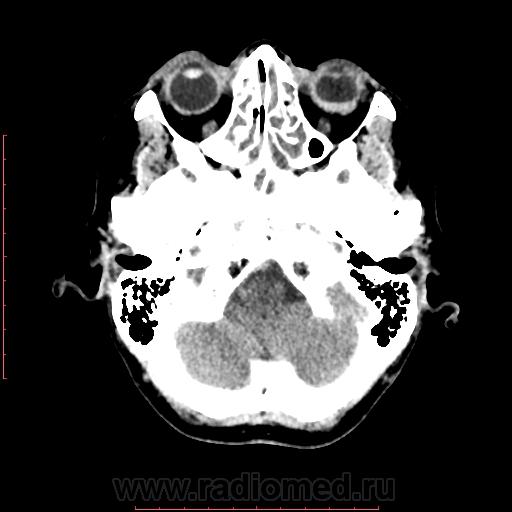

КТ орбит. Образование левого глазного яблока

Женщина 57 лет обратилась с жалобами на снижение зрения левого глаза. На УЗИ объемное образование левого глаза. Написал DDs меланома, ретинобластома.

Меланома - да, надо исключать. (наиболеее вероятно).

Рентинобластома - крайне маловероятна (после 5-ти лет эта опухоль практически не встречается).

Я тоже склоняюсь больше в сторону меланомы. Ретинобластома врожденная опухоль, в 90% случаев диагностируется как вы и сказали до 5 лет, у взрослых встречается редко и в 95% содержит обызвествления, но в дифф.ряд указал на всякий случай.